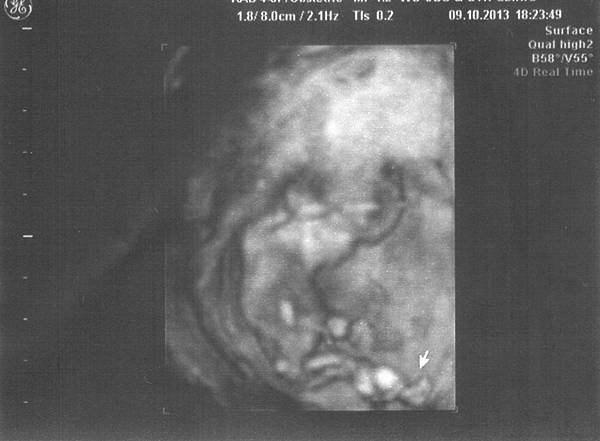

14w0d-116w6d-115w2d-115w2d-216w6d-1